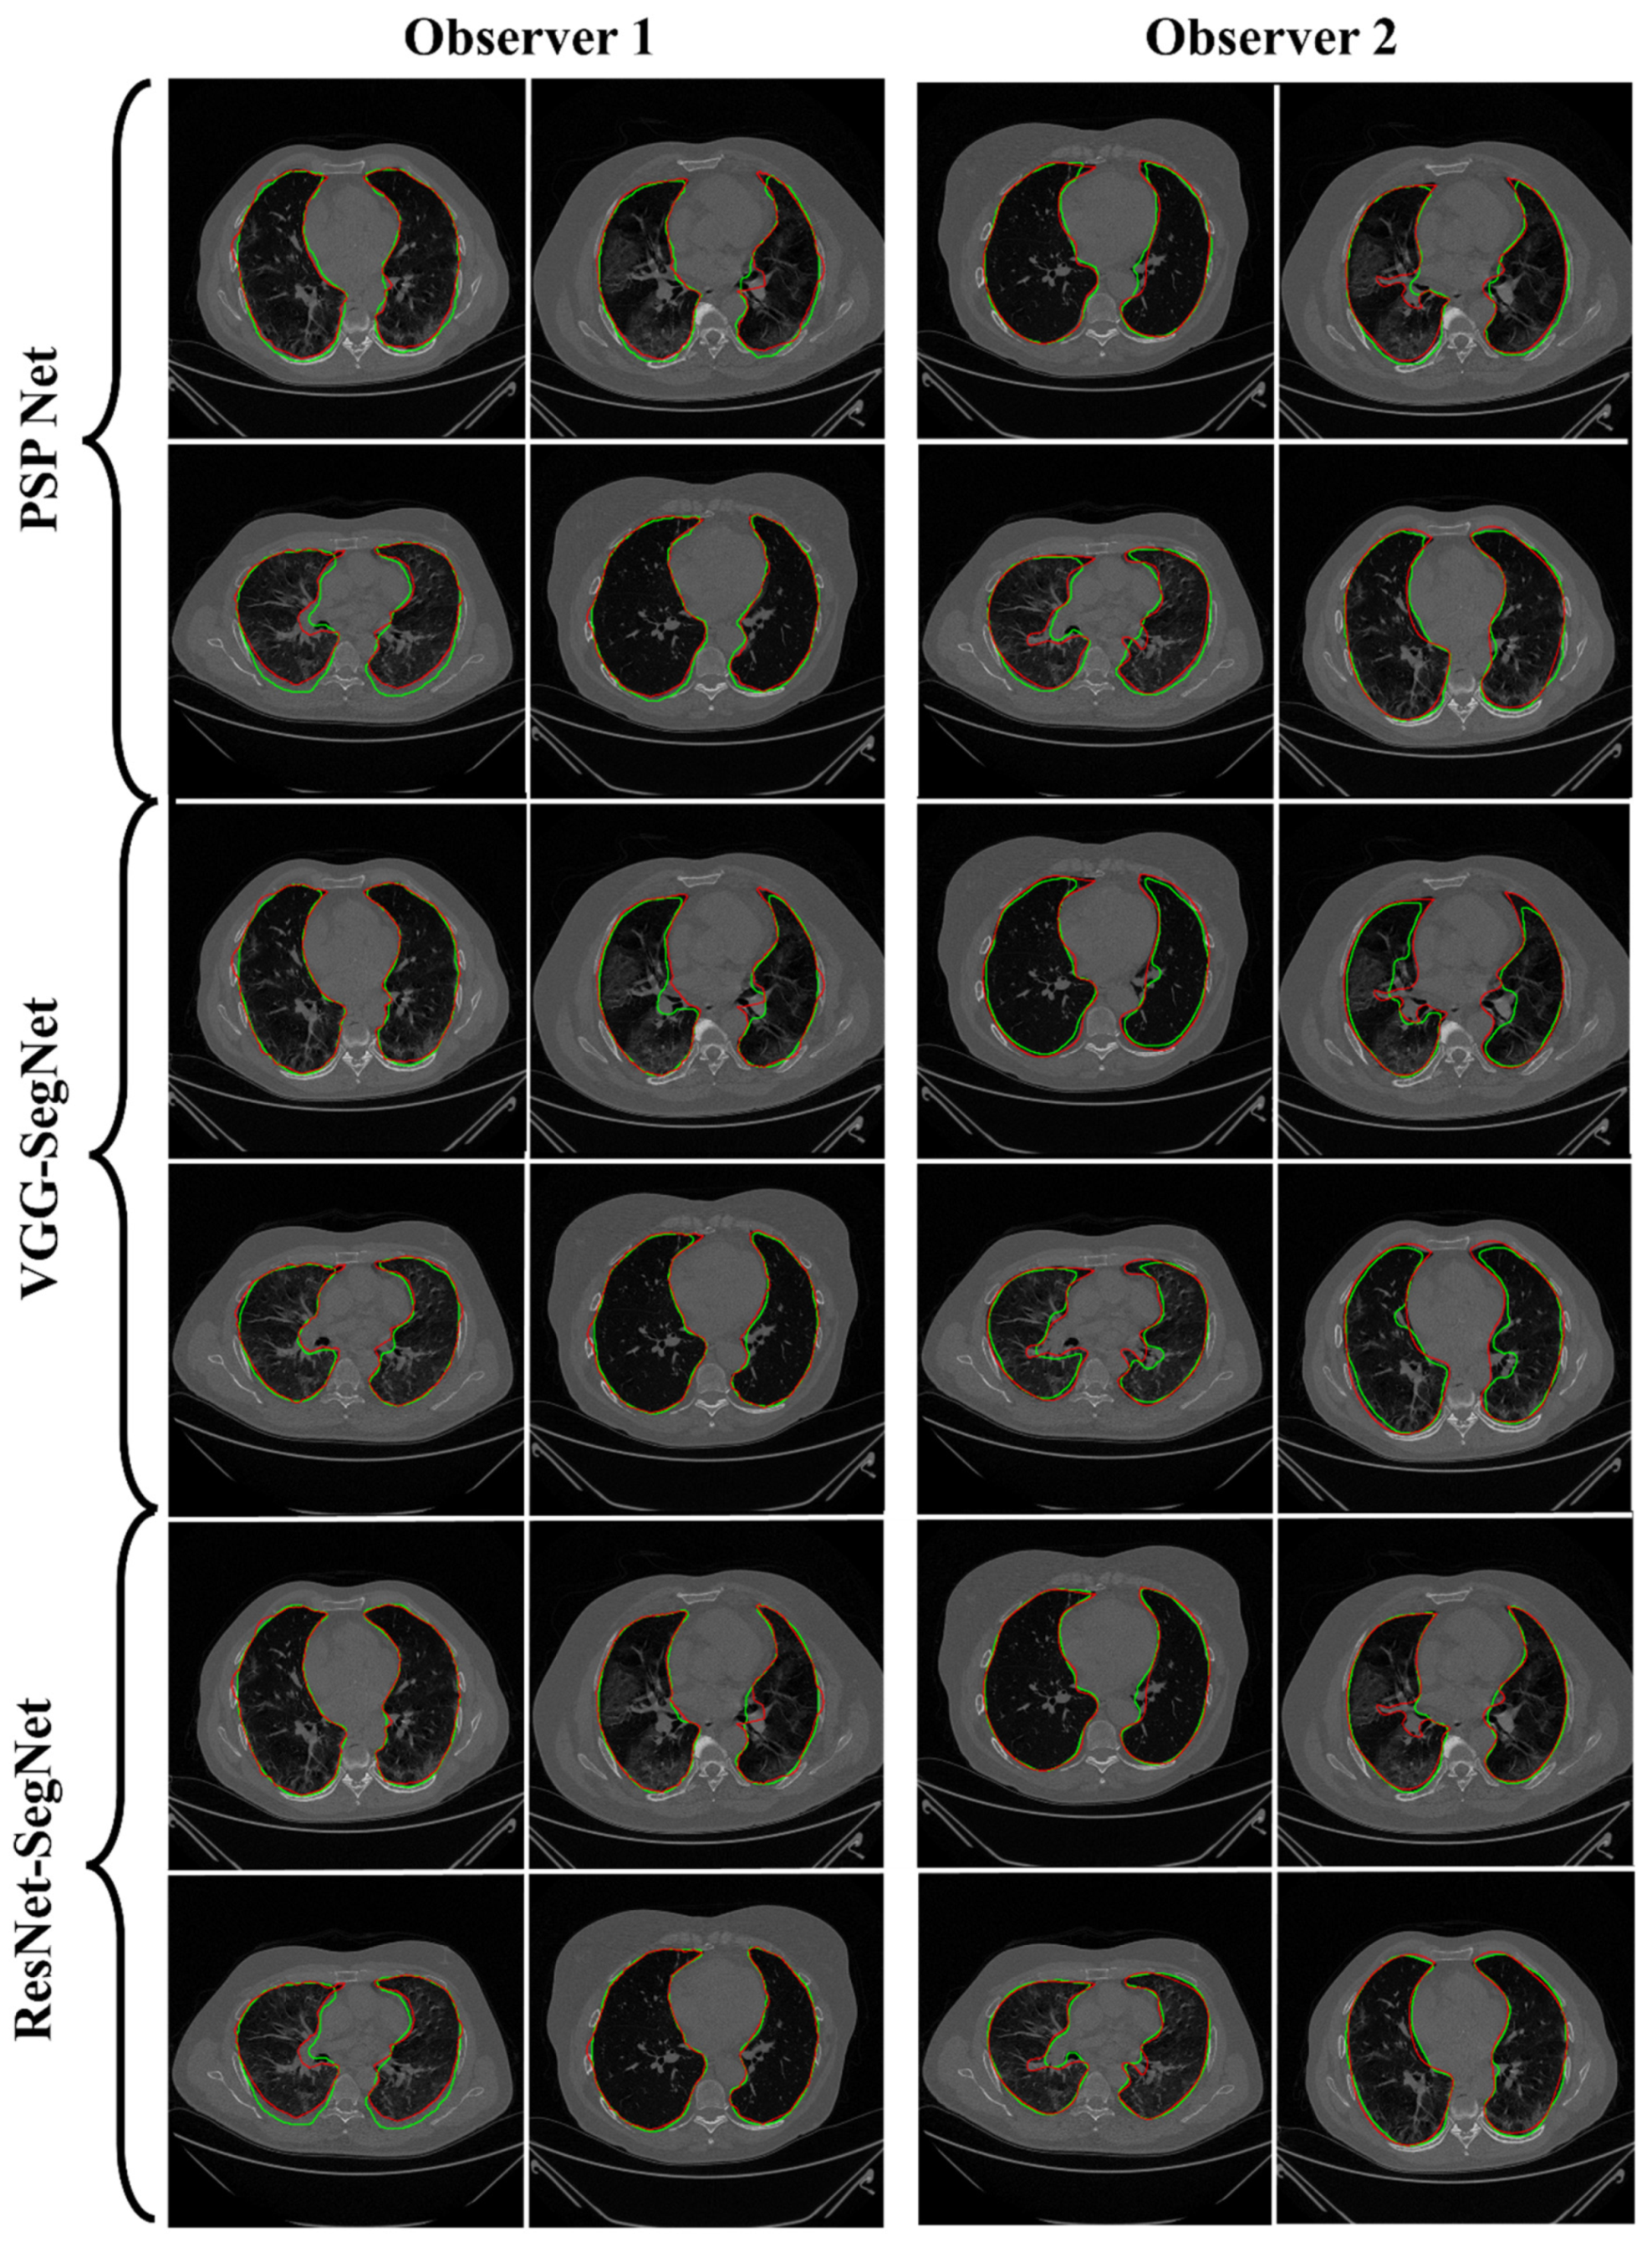

4.2.1. Lung Boundary and Long Axis Visualization